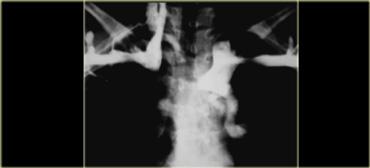

Hình ảnh này thuộc về một bệnh nhân mắc hội chứng Boerhaave.

X-quang ngực cho thấy tràn khí trung thất (các mũi tên).

Chụp thực quản cản quang cho thấy thuốc cản quang tan trong nước thoát ra ngoài lòng mạch ở nửa ngực trái (dấu hoa thị).

Thủng hầu như luôn xảy ra ở phía trái của thực quản đoạn xa.

X-quang cho thấy khí trung thất, tràn dịch và sau đó là tràn khí màng phổi.

Chụp thực quản cản quang được sử dụng để xác nhận rò rỉ, trước tiên dùng thuốc cản quang tan trong nước, sau đó dùng barium nếu không phát hiện rò rỉ.